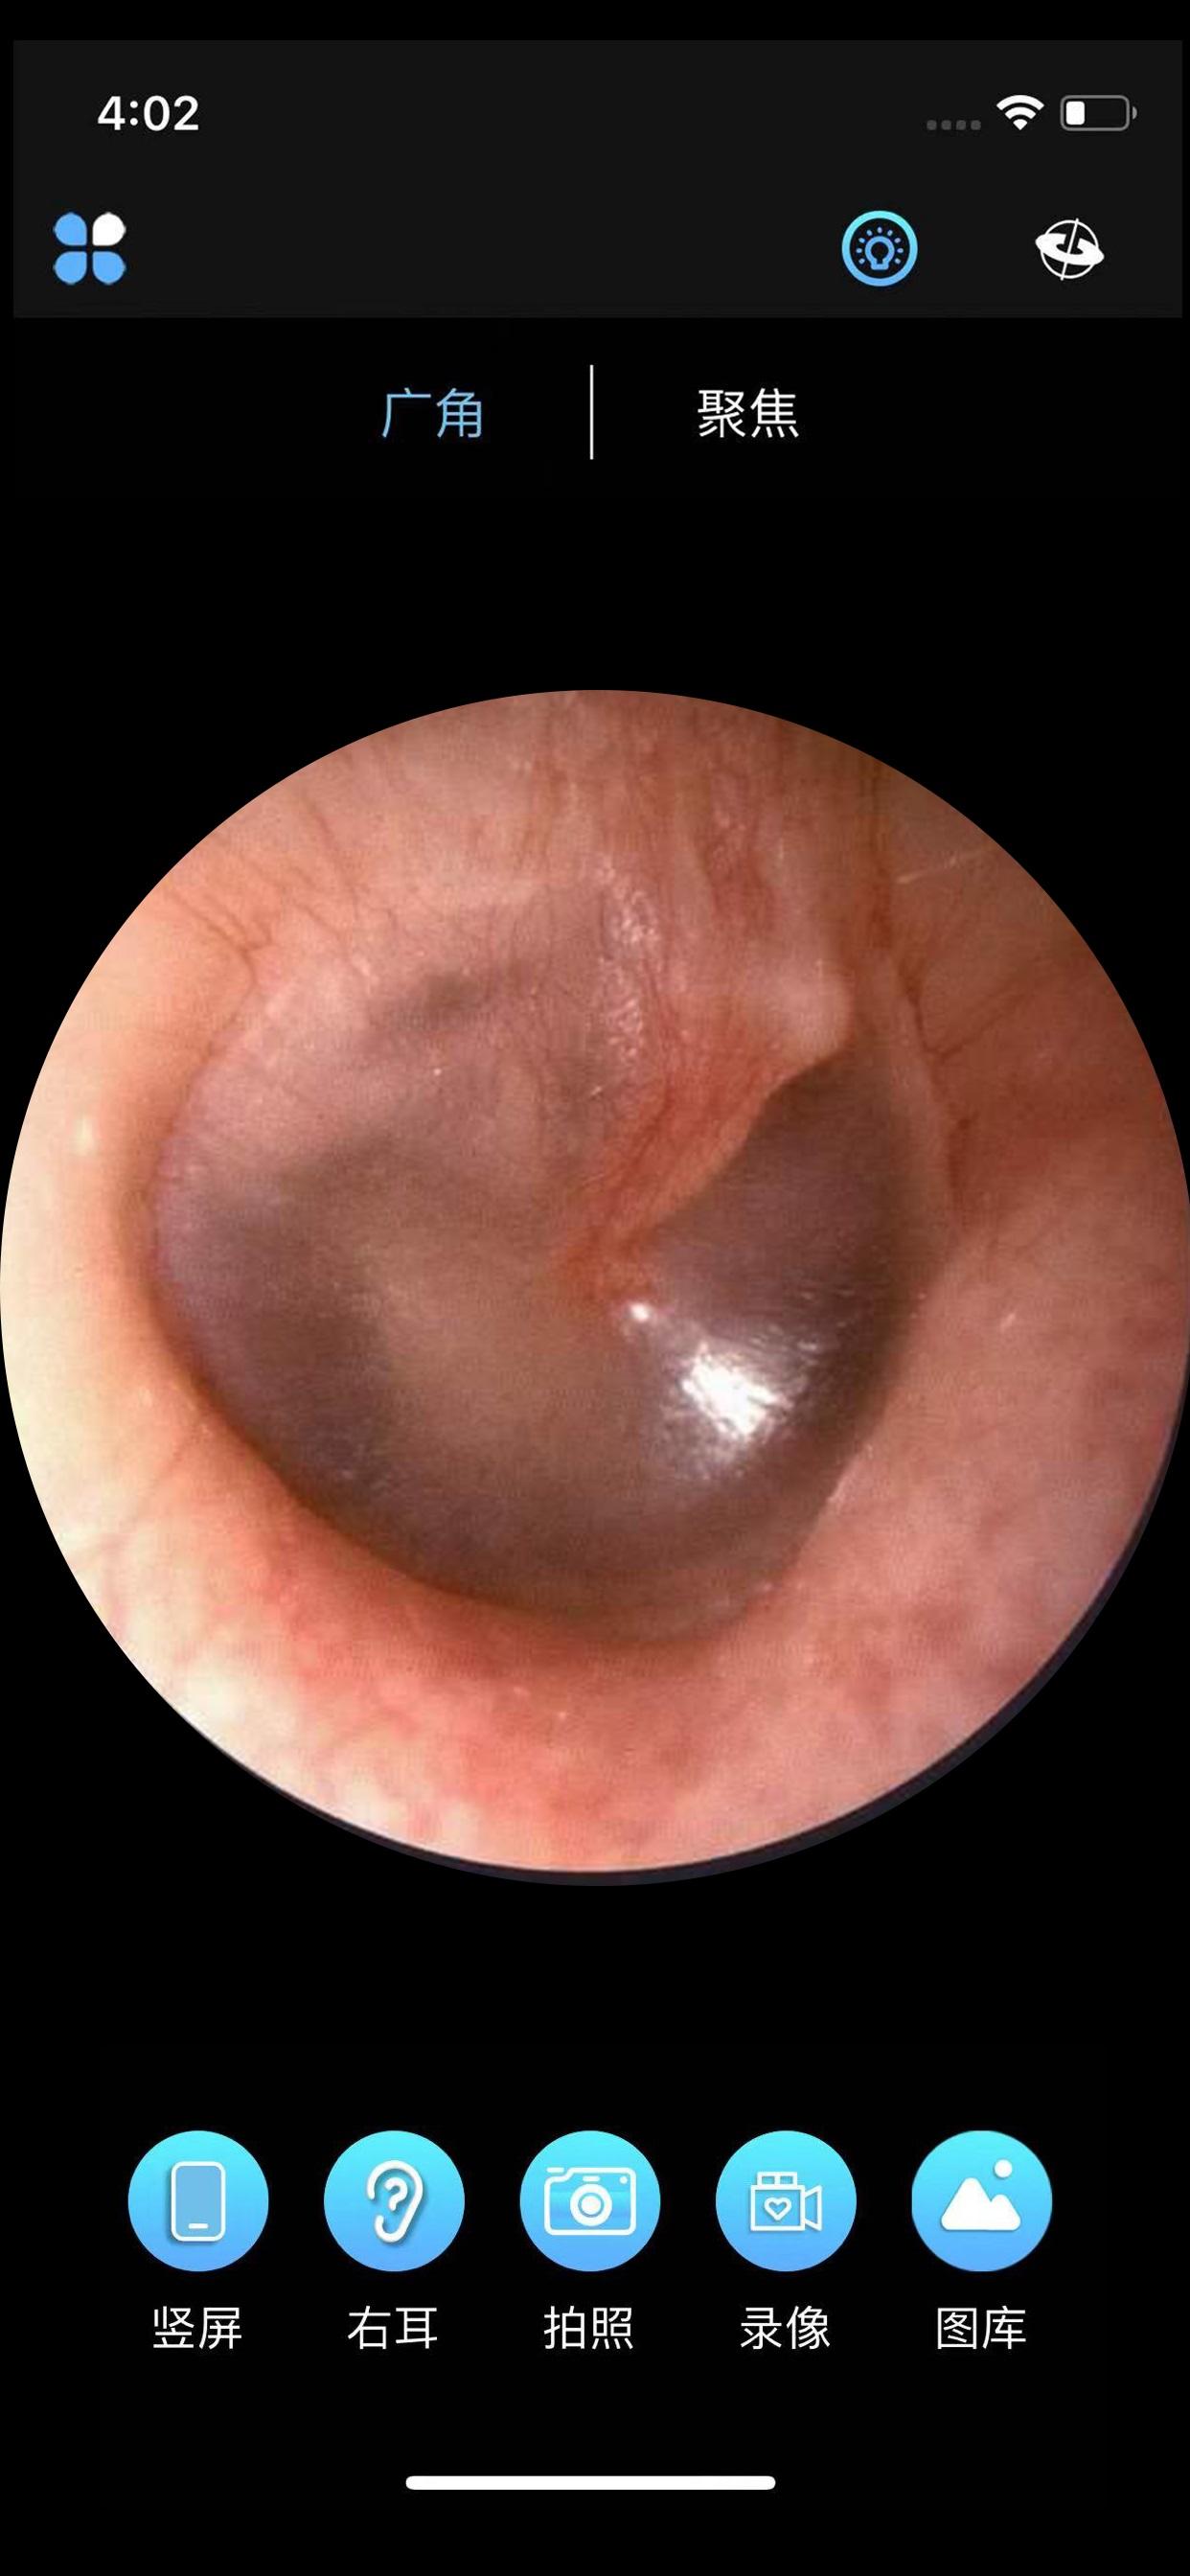

ALK的核心功能之一是其强大的连接性能。通过WiFi技术,ALK能够轻松连接到配套的采耳设备,确保稳定的信号传输。无论是室内还是室外环境,用户都可以享受到流畅的操作体验。连接成功后,ALK会自动启动高清图像显示模式,将采耳过程以1080P甚至更高的分辨率呈现在用户的手机屏幕上。这种高清显示不仅提升了视觉效果,更重要的是让用户能够更加直观地了解耳朵内部的情况,确保采耳的安全性和准确性。

为了满足不同用户的需求,ALK提供了多种智能调节功能。首先,ALK支持广角和聚焦调节,用户可以根据实际情况选择最适合的角度和焦距,确保采耳过程中的每一个细节都能清晰可见。其次,ALK内置了陀螺仪传感器,能够根据手机的姿态自动调整画面方向,无论是横屏还是竖屏使用,都能获得最佳的观看体验。最后,ALK还特别设计了左耳右耳切换功能,用户只需轻轻一点,即可快速切换左右耳视角,操作简单便捷。